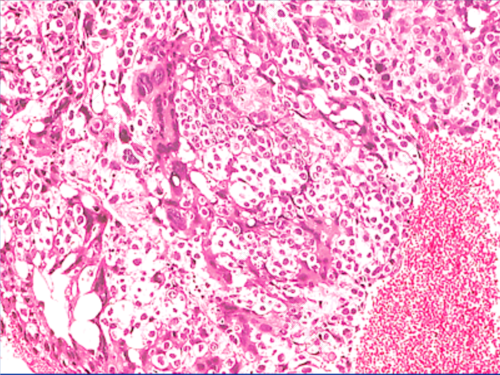

女性孕后检查发现了滋养细胞异常要考虑妊娠出现了不正常情况。而与子宫滋养细胞相关的疾病较多,孕后最常见为葡萄胎,而且有些可能和恶性葡萄胎有关,还有胎盘植入发生恶变、绒毛膜癌、以及输卵管部位出现恶性病变等。这类疾病都可导致女性体内hcg分泌异常增高,甚至可比正常值明显高出10~20倍以上。

女性孕后滋养细胞异常确诊为葡萄胎后,应尽早时间做手术治疗。并且要将妊娠组织送去做病理活检,如果通过病理检测结果确定属于良性葡萄胎,在术后恢复一年有备孕需求可考虑再次怀孕。若确诊为恶性葡萄胎时要在随后做严密跟踪检查以及针对性化疗。